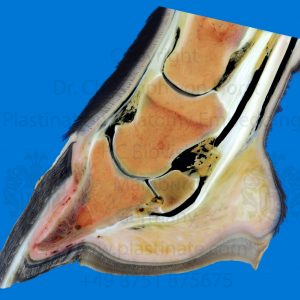

Description

“Sample-Trial-Test” Outlet Offer without detailed description. Please check the images for anatomical structures and details.

Make a judgement for yourself:

Is this outlet plastinate okay for me?

Do I see the structures, which I am interested in?

Is this the right preparation quality and plastination technique for my purposes (exhibition, teaching, curiosities collection, etc.)?